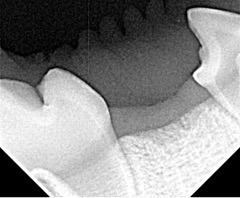

Abbildung 15: Nachweis eines fehlenden Zahnes mittels Röntgenbild.

Zwischen den beiden sichtbaren Zähnen ist keine Zahnanlage zu erkennen.